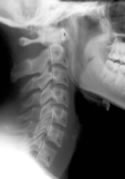

Identifying these ligamentous injuries, however, can be difficult. The ligaments themselves may be detected on MRI, but they cannot be seen on normal radiographs. It is more likely that the ligament injury will result in changes to the alignment of the cervical spine, and that can be detected with plain films.

The authors of this current study began with 13 patients who had been in a car crash. They obtained a neutral cervical radiograph taken in the natural standing position. Then, each patient was treated by a chiropractor. The patients had an average age of 24, and the average number of chiropractic adjustments was 17.7.

After a period of care, neutral radiographs were again taken, and both the pre- and post-treatment films were evaluated by a second chiropractor who was blinded to which films belonged to which patient.

The cervical curve was measured in each of the x-rays.

10 of the 13 patients showed an increase in the cervical lordosis found on x-ray. The average increase found in the patients was 6.4°.

One patient showed no change and two patients showed a decrease in cervical lordosis.